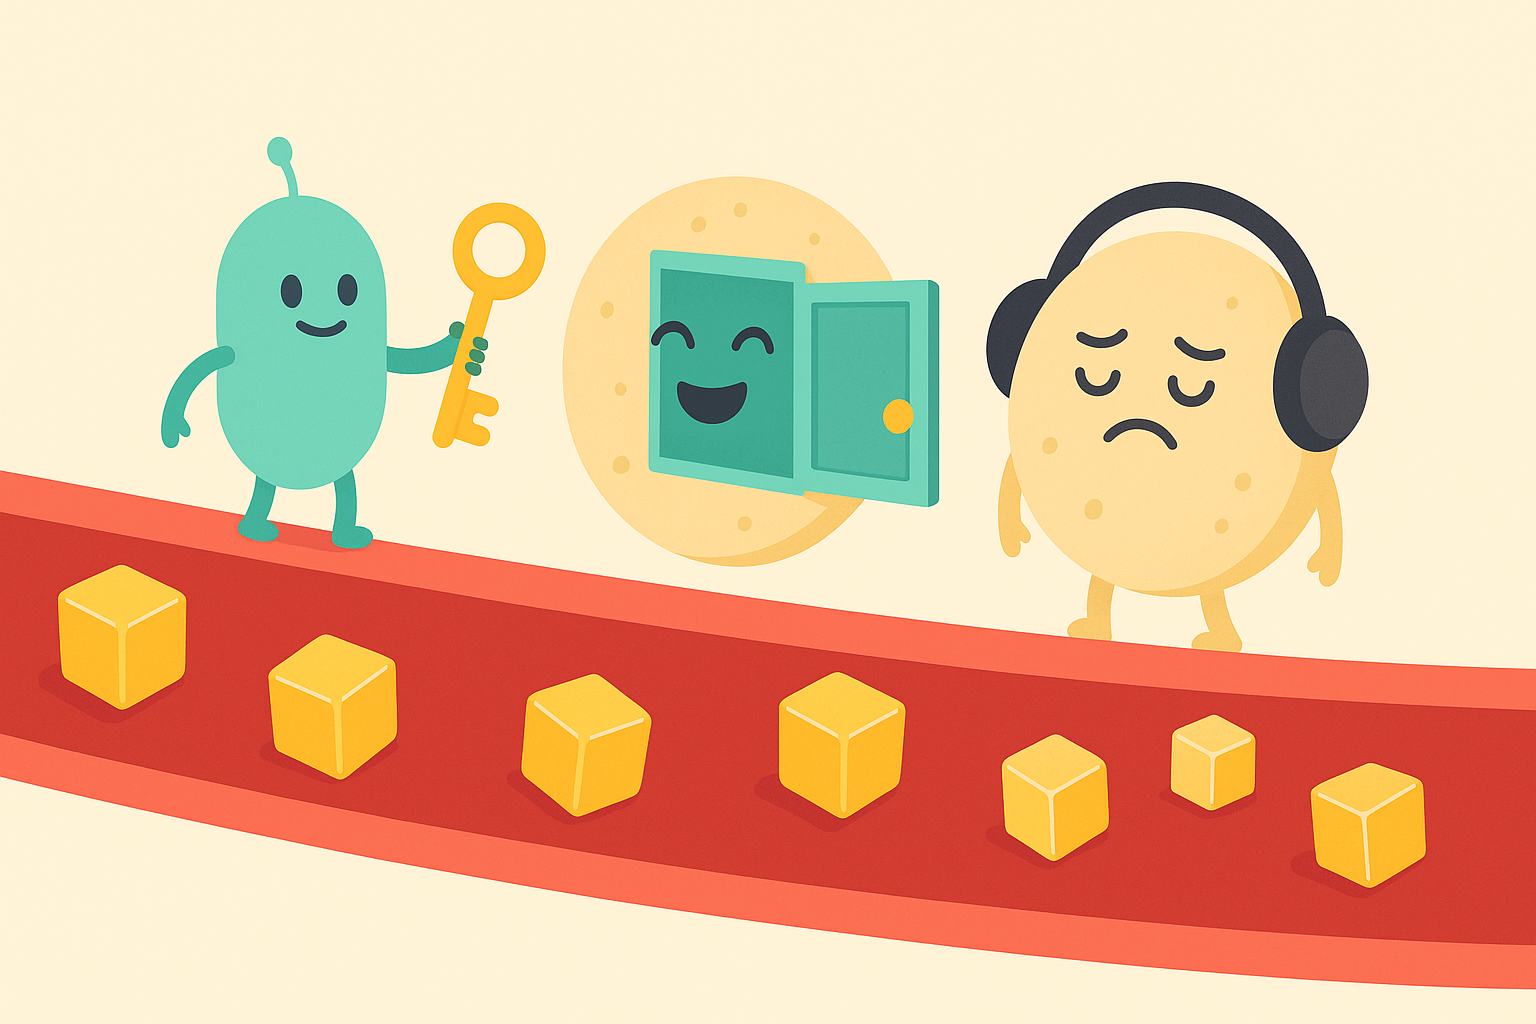

Un intrus nommé Willie vient de franchir votre peau. En quelques secondes, des milliards de soldats microscopiques se mobilisent : mangeurs voraces, espions futés, tireurs d’élite et tueurs à gages. Le champ de bataille ? Votre corps. Le prix ? Votre vie. Bienvenue dans la guerre silencieuse qui se déchaîne chaque fois que vous éternuez.